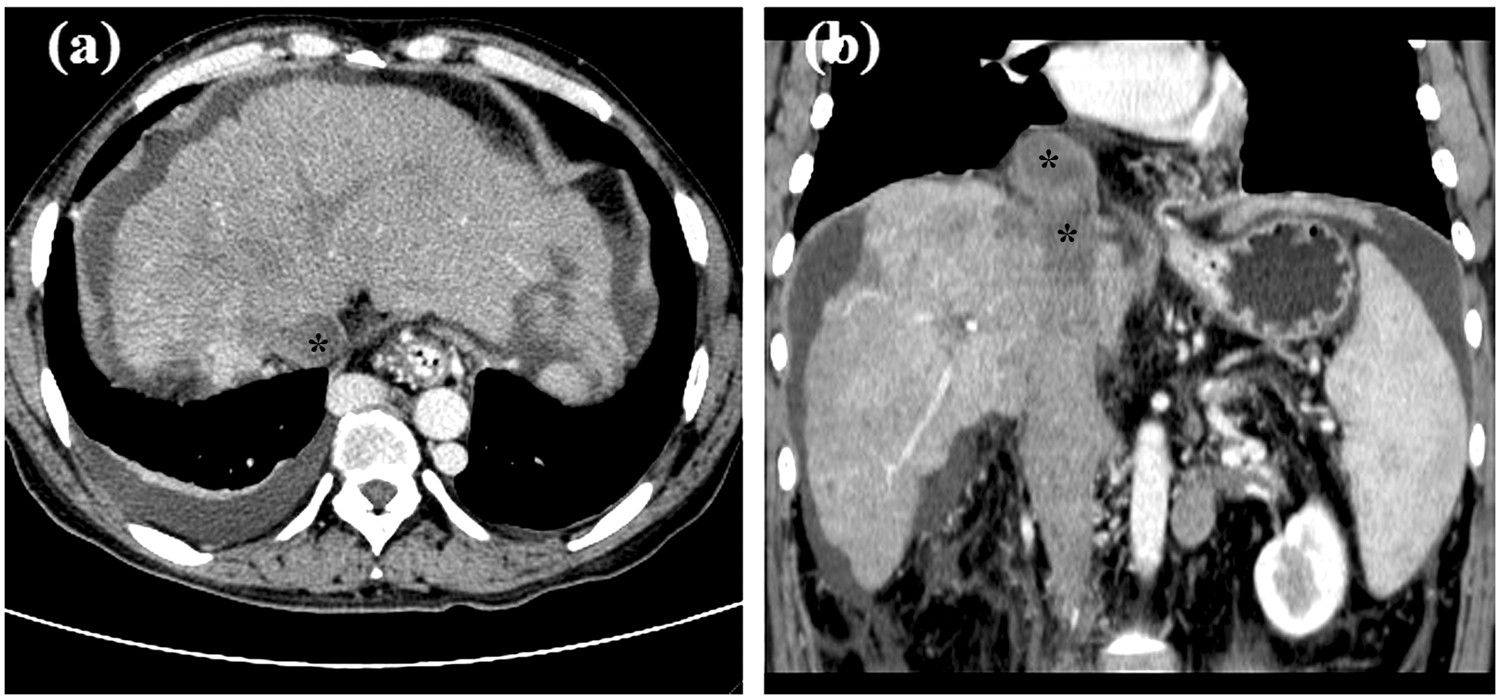

Preoperative CT scanning. (a) Liver cirrhosis caused by BCS, hydrothorax, and can be seen in the cross section of CT. (b) Segmental occlusion of IVC with thrombus was shown in coronal section view. * indicated thrombus.